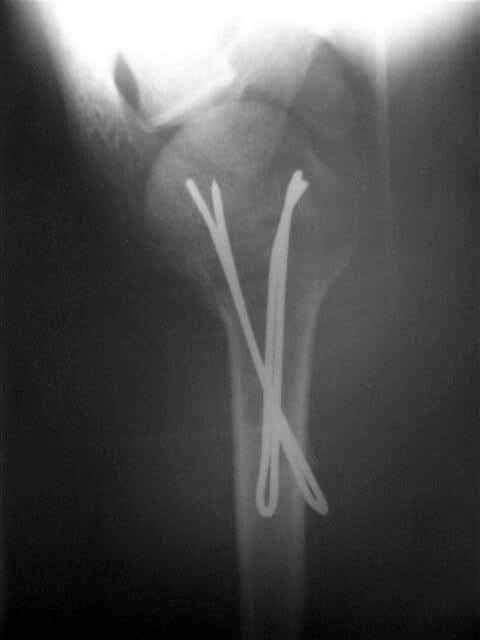

Посылаю послеоперационные Рг граммы.

Я и сам доволен результатом. В предпоследнем письме я кратко описал ход операции - закрыто репонировать не удалось( 2 недели с момента травмы и 1 неделя после неудачной репозиции) после удаления пучков спиц, пришлось сделать - 2см разрез на уровне перелома и с помощью периостального элеватора (золотое правило механики) *одеть* головку на дистальный отломок.

Спицы проводил через старые отверстия, вращая пучок импактором- направителем при его введении в головку.